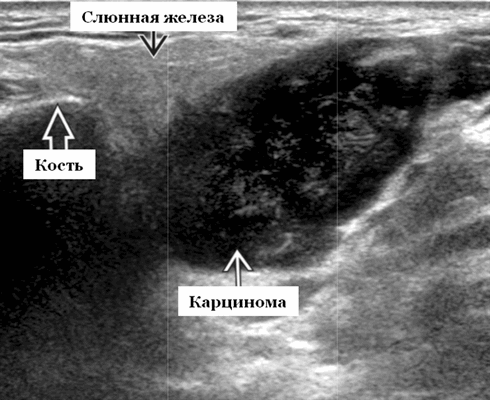

Данные УЗИ слюнных желез при карциноме

- Увеличенное солидное образование околоушной при ультразвуковом сканировании (примерно 75%) или поднижнечелюстной железы (примерно 25%)

- Особенности визуализации неспецифические

- Нечеткие или четко определенные границы.

- Гипоэхогенная, гомогенная или гетерогенная эхоструктура на УЗИ

- Отмечается внутренняя васкуляризация на цветном доплеровском исследовании.

- Могут наблюдаться аномальные интрапаротидные, перипаротидные, шейные лимфатические узлы.

Общие характеристики при ультразвуковом сканировании

- Лучший диагностический признак на УЗИ слюнной железы - Увеличенное солидное образование околоушной или поднижнечелюстной железы

Результаты ультразвукового исследования слюнной железы

- Серошкальное УЗИ. Одиночное солидное образование в паренхиме околоушной или подчелюстной железы. Может иметь хорошо выраженные, дольчатые или плохо очерченные / инфильтративные границы. Гипоэхогенная структура по отношению к паренхиме слюнной железы. Общее улучшение ультразвукового изображения задних структур. Иногда центральный кистозный компонент представляет некроз. Могут наблюдаться связанные аномальные интрапаротидные, перипаротидные, шейные лимфатические узлы

- Цветной допплер. Внутриузловая васкуляризация от умеренной до выраженной